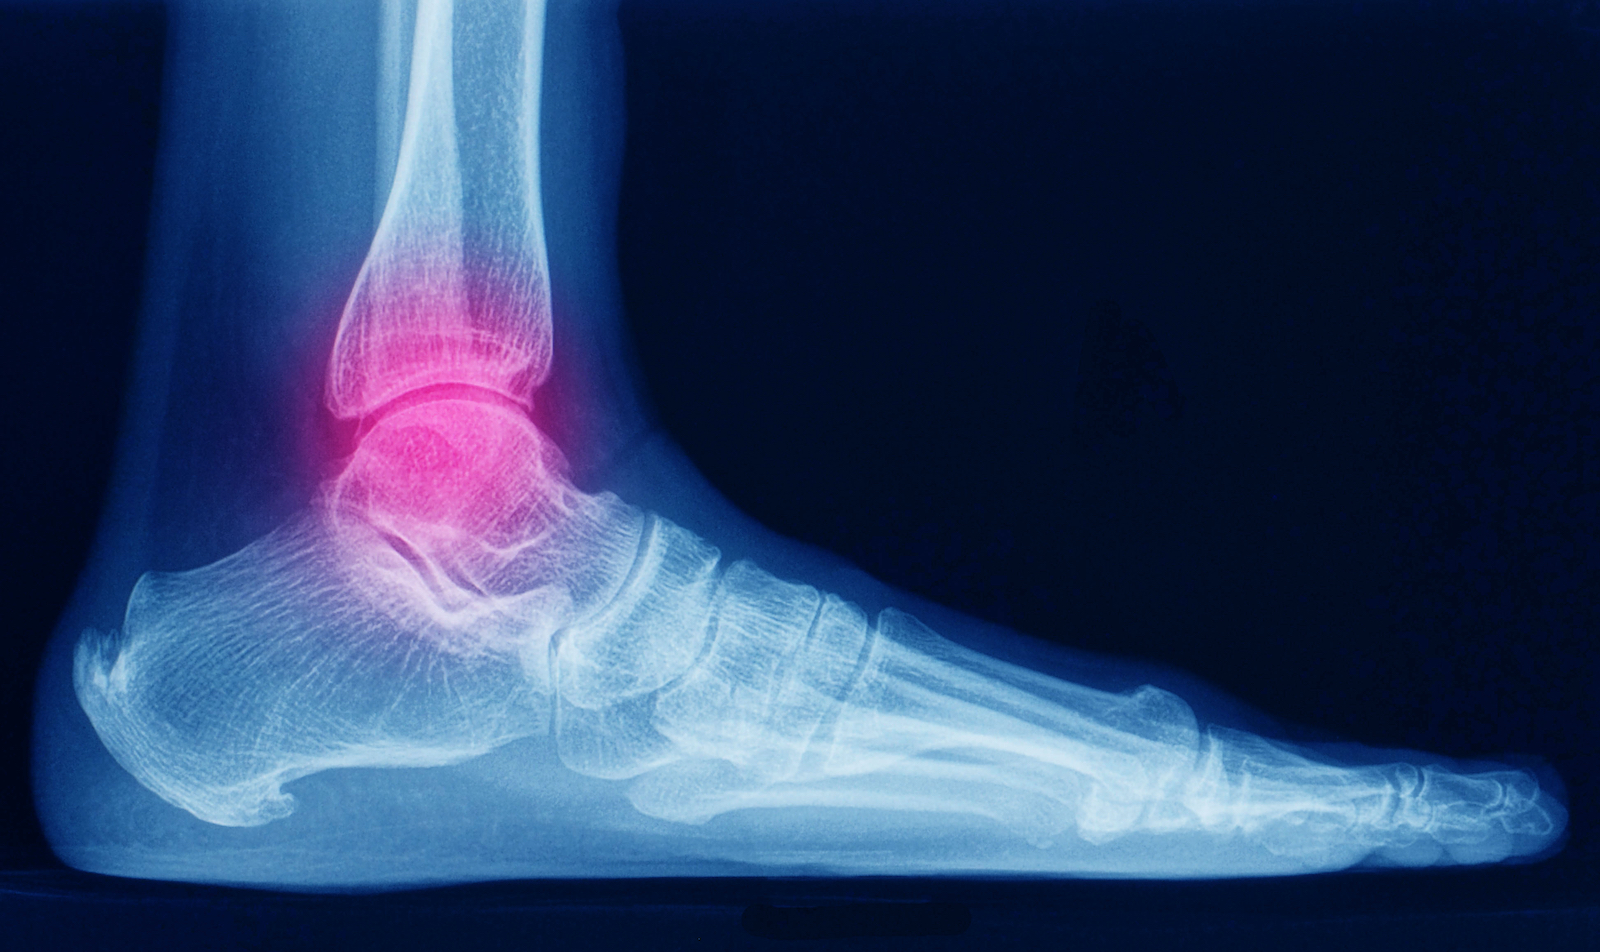

Ein großes Problem der Erkrankung sind Mikroblutungen in Gelenken. Oftmals bemerken die Betroffenen diese Minimalblutungen nicht, und die Gelenke werden auf Dauer geschädigt. Viele Patient:innen besitzen so genannte Zielgelenke – Gelenke, die immer wieder von Mikroblutungen betroffen sind. Hier entwickeln sich am ehesten dauerhafte Schäden. Bei sportlich aktiven Erkrankten ist häufig das Sprunggelenk betroffen. Dauerhafte Einblutungen führen dazu, dass Patient:innen Schmerzen beim Stehen und Gehen entwickeln, die Mobilität wird eingeschränkt.

Rote warme Gelenke – viele Hämophilie-Patient:innen kennen dieses Gefühl. Auslöser hierfür sind Gelenkblutungen. Je nach Blutmenge kann es vorkommen, dass der Körper mit der Entfernung der Erythrozyten überfordert ist und es zu temporären Ablagerungen kommt. Hierdurch kann eine fortlaufende Entzündungskaskade in Gang gesetzt werden. Gelenkspülungen können für Hämophilie-Patient:innen eine Möglichkeit sein, das freigesetzte Blut schnell aus dem Gelenk zu entfernen. Dabei ist der Eingriff der Gelenkspülung selbst klein – Patient:innen müssen kaum mit Risiken rechnen.